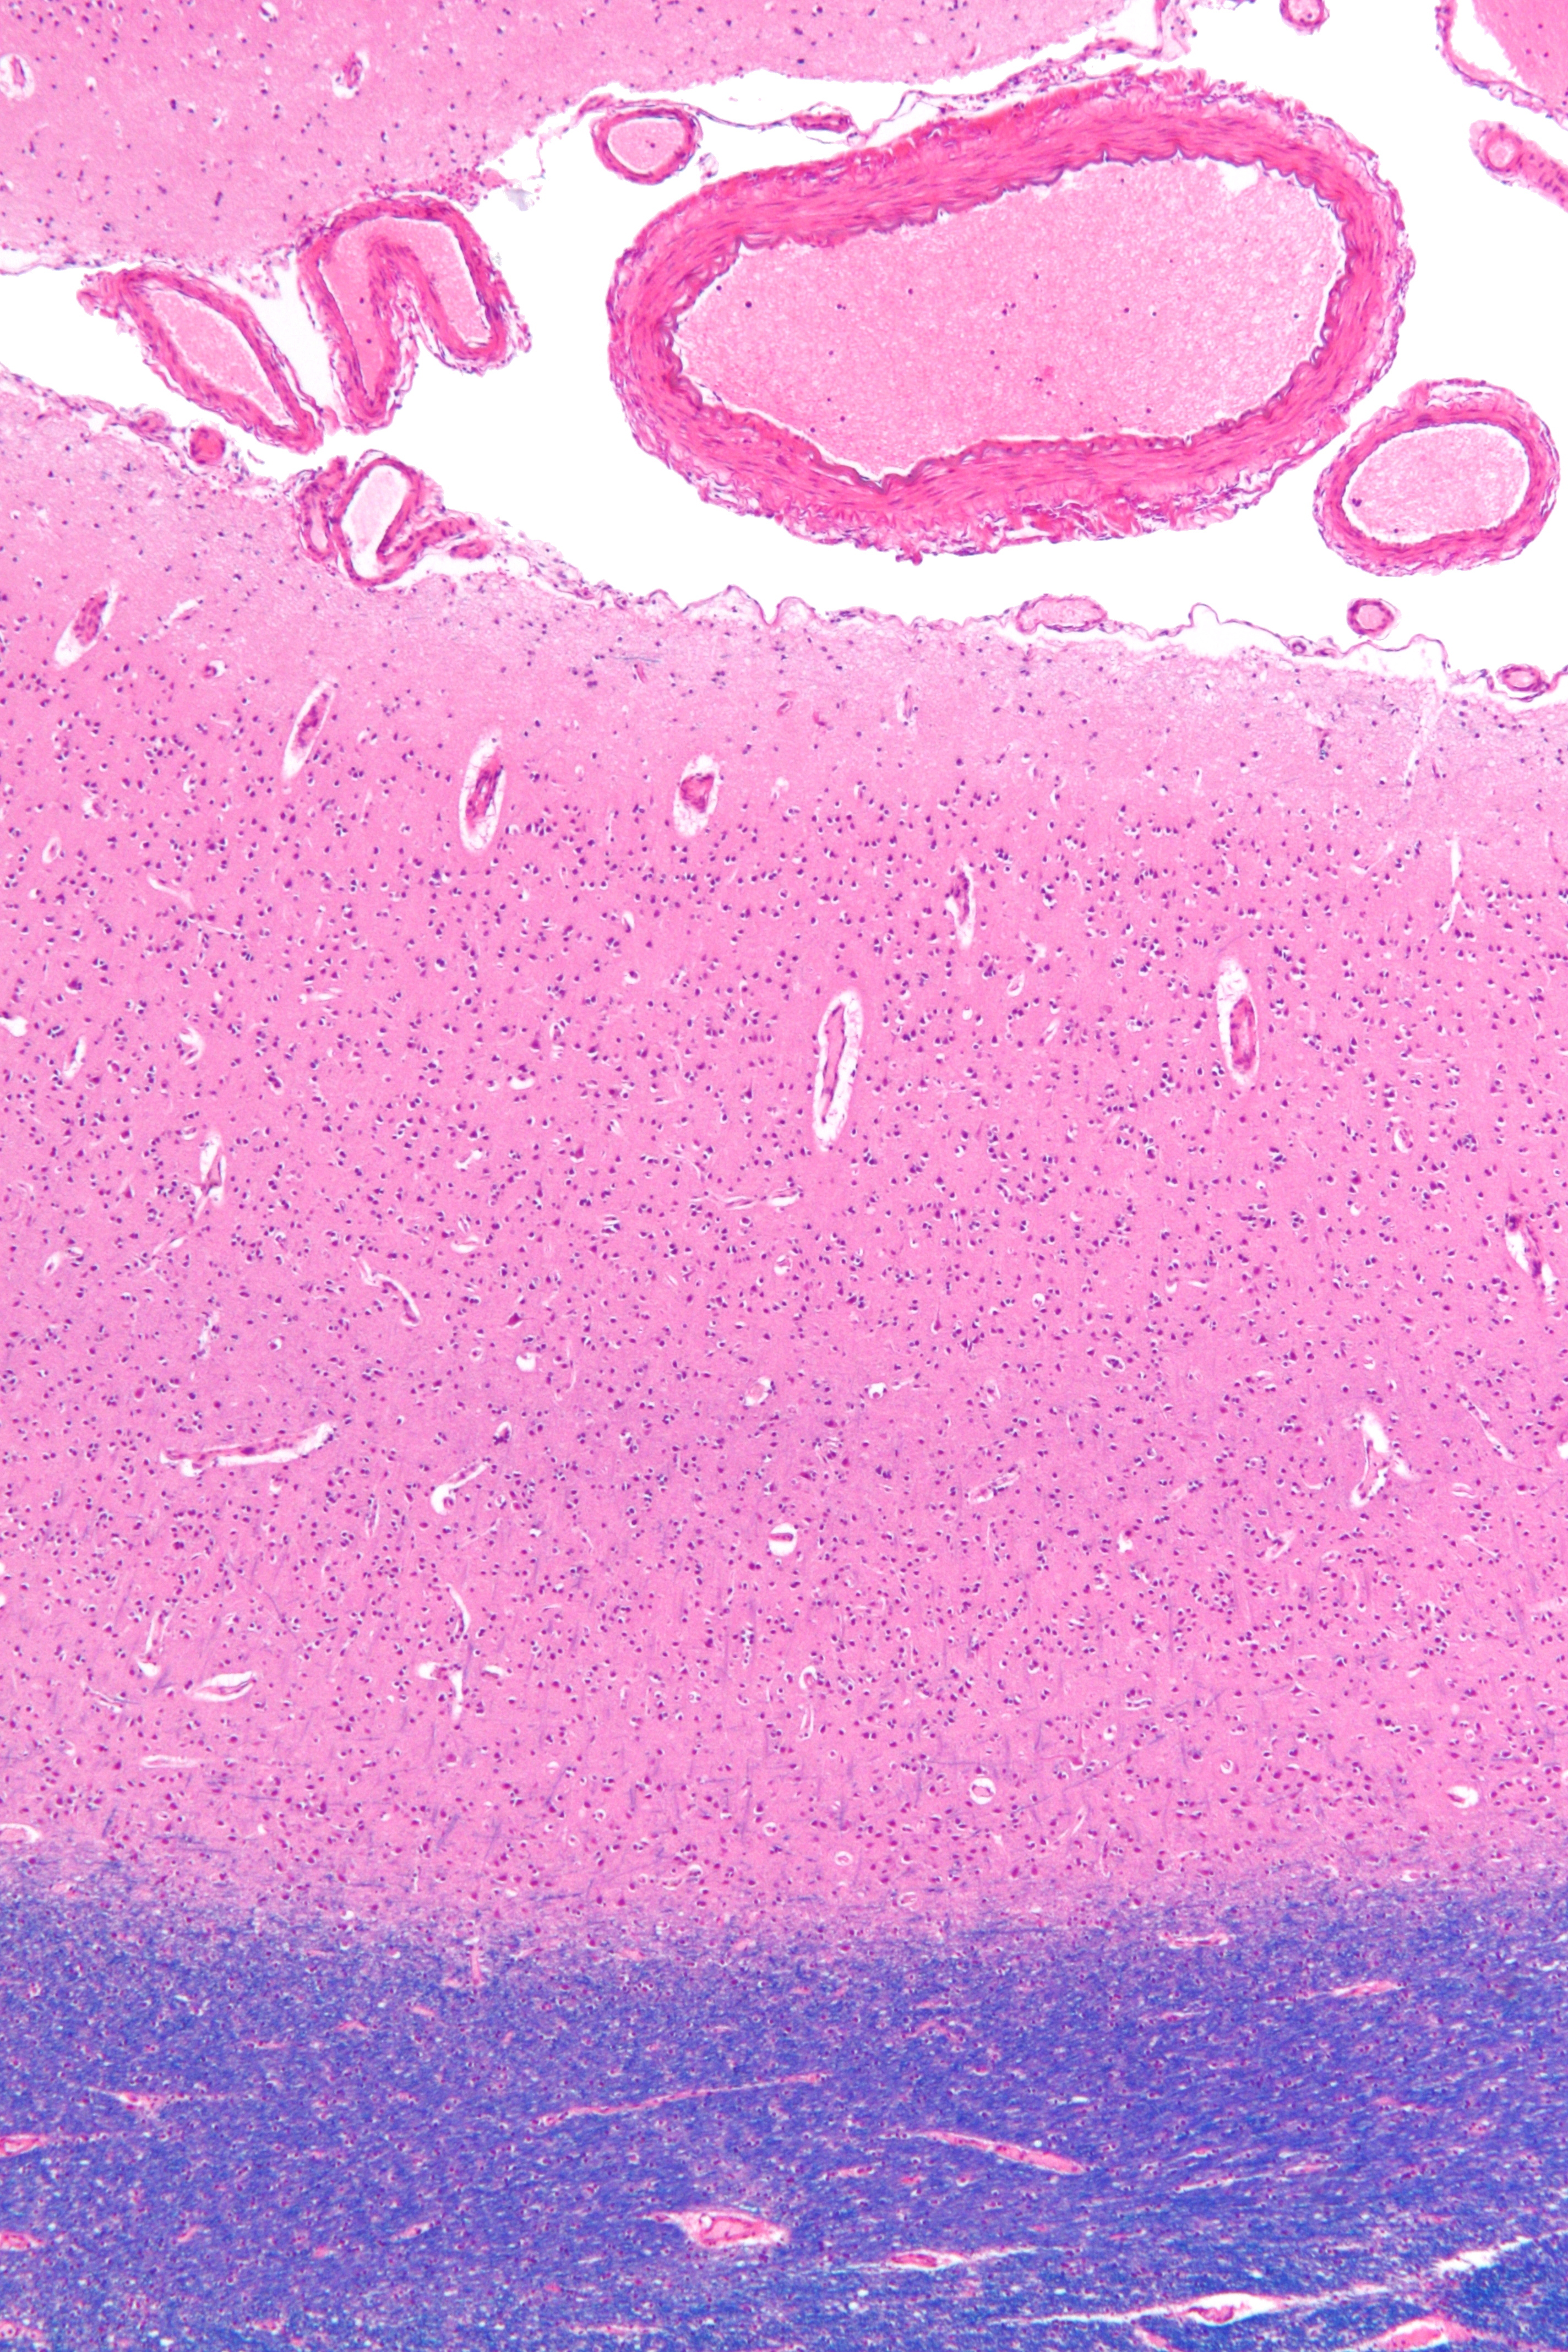

현미경 사진은 시각 피질(주로 분홍색)을 보여준다. 피질하 백색질 (주로 파란색)은 이미지 하단에서 볼 수 있다. HE-LFB 염색.